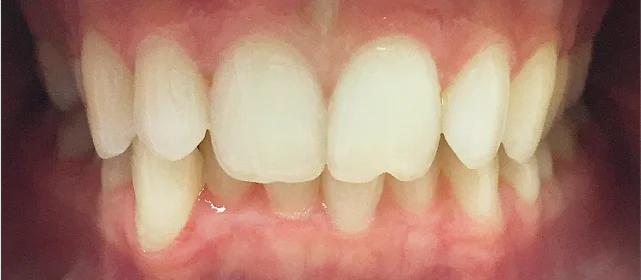

Зубы выровнены, смыкание нормализовано. Установлены несъёмные ретейнеры на обе челюсти, изготовлены ретенционные капы. Пациентка предварительно проконсультирована ортопедом онлайн.

Решение: Поставили элайнеры 3D Smile на обе челюсти. Лечение заняло 4 года и потребовало нескольких последовательных этапов коррекции. Капы менялись каждые 1–2 недели, на контрольных визитах отслеживали прогресс и выдавали новые наборы. Зубы встали в правильное положение, смыкание нормализовалось. Зафиксировали ретейнеры на обе челюсти, изготовили ретенционные капы. Пациентка прошла онлайн-консультацию с ортопедом для оценки дальнейших шагов.

Лечение потребовало нескольких последовательных этапов — каждый дозаказ кап уточнял положение зубов, которые не полностью отреагировали на предыдущий курс. Элайнеры 3D Smile позволяют работать поэтапно, корректируя план по ходу. Результат получен, ретейнеры зафиксированы. Рекомендовала пациентке консультацию ортопеда для оценки состояния зубов после лечения